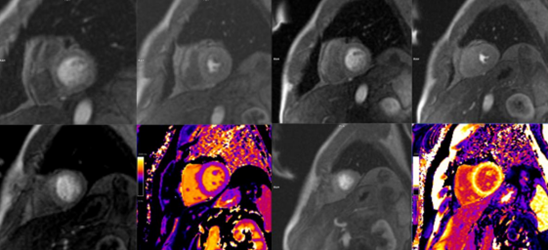

Recientemente el Hospital Universitario Quirónsalud Valle del Henares realizaba su primera Resonancia cardíaca de perfusión, también llamada Resonancia de estrés.

Como destaca la Dra. Angélica Romero Daza, Jefa de la Unidad de Imagen Cardíaca avanzada, "la resonancia de perfusión miocárdica es una prueba de imagen cardíaca no invasiva, útil en el diagnóstico y valoración de pacientes con cardiopatía isquémica o sospecha de la misma".

Se trata de una técnica con gran evidencia científica que ofrece gran sensibilidad y especificidad a la hora de diagnosticar enfermedad coronaria significativa y su repercusión sobre el músculo del corazón, dado que, además de detectar falta de riego del corazón (isquemia), también aporta información sobre la anatomía, función y cicatrices del mismo. Todo ello con una gran calidad y definición de imagen y sin la necesidad de radiación, por lo que se está convirtiendo en la prueba de referencia para el estudio de la cardiopatía isquémica.

Esta prueba no requiere interpretación del electrocardiograma, por lo que es especialmente útil en pacientes con alteraciones electrocardiográficas que dificulten la interpretación de otras pruebas de detección de isquemia. Para realizarla es necesario administrar, por vía venosa, un agente vasodilatador (Regadenoson) seguidamente de contraste de gadolinio y obtener unas imágenes mediante la resonancia para detectar defectos de riego miocárdico.